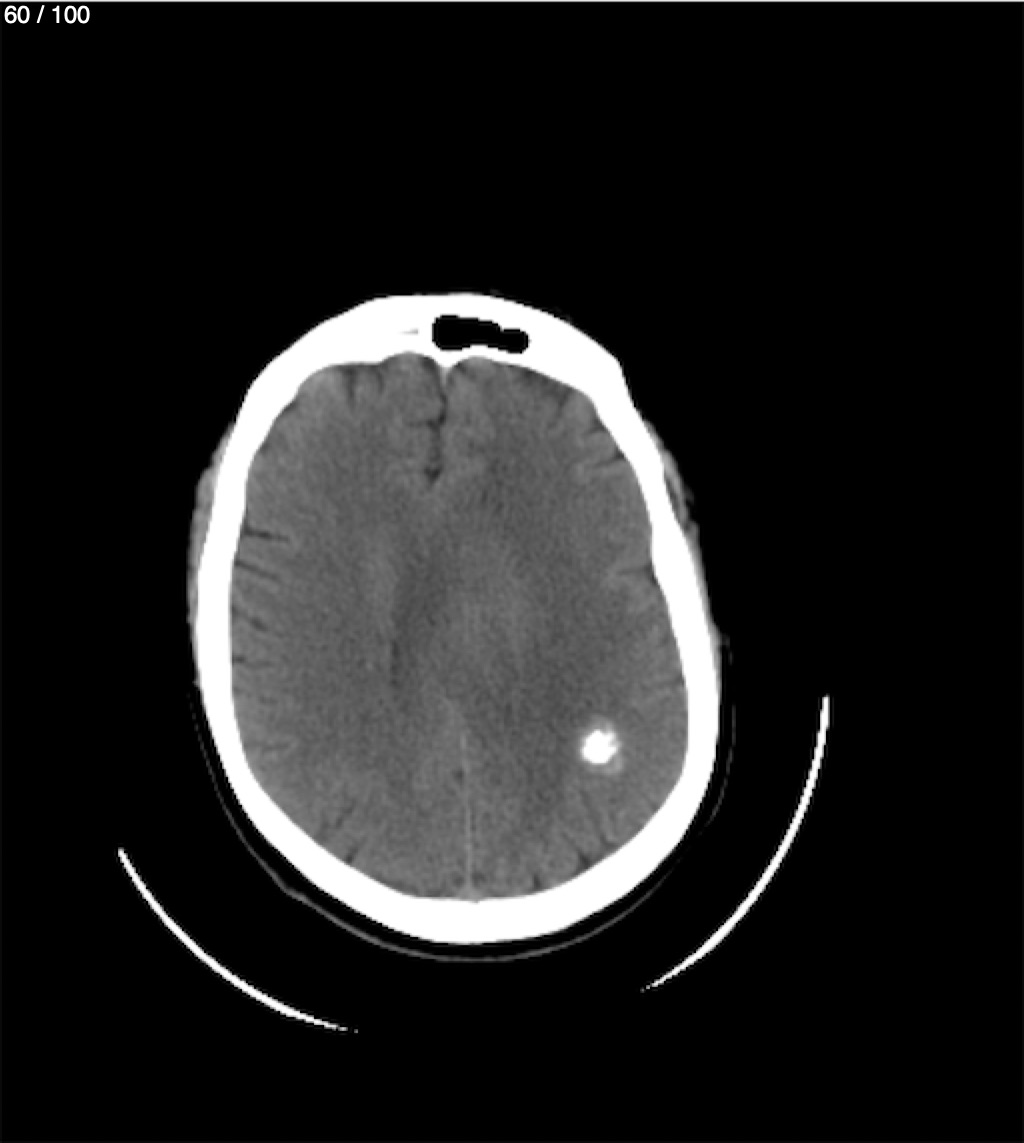

Valentin Perez Gomez 69A - T.C Craneo